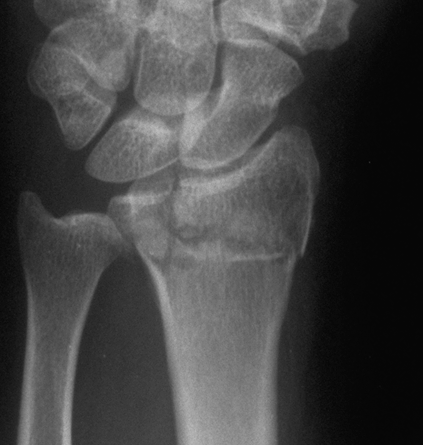

Case 2 Preop